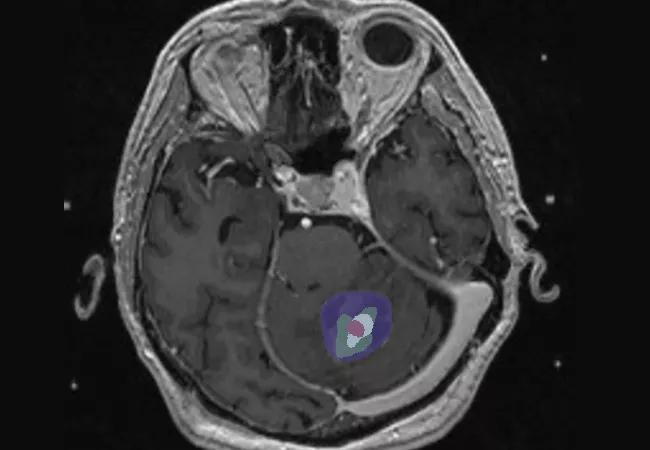

• The median change in tumor volume at three-month follow-up MRI after 2-SSRS was a 54 percent reduction from baseline (P < .001). (See Figure 1 for an example case.)

Figure 1. Tumor size over time in one of the patients from our study (image courtesy of neurosurgery resident Ghaith Habboub, MD).